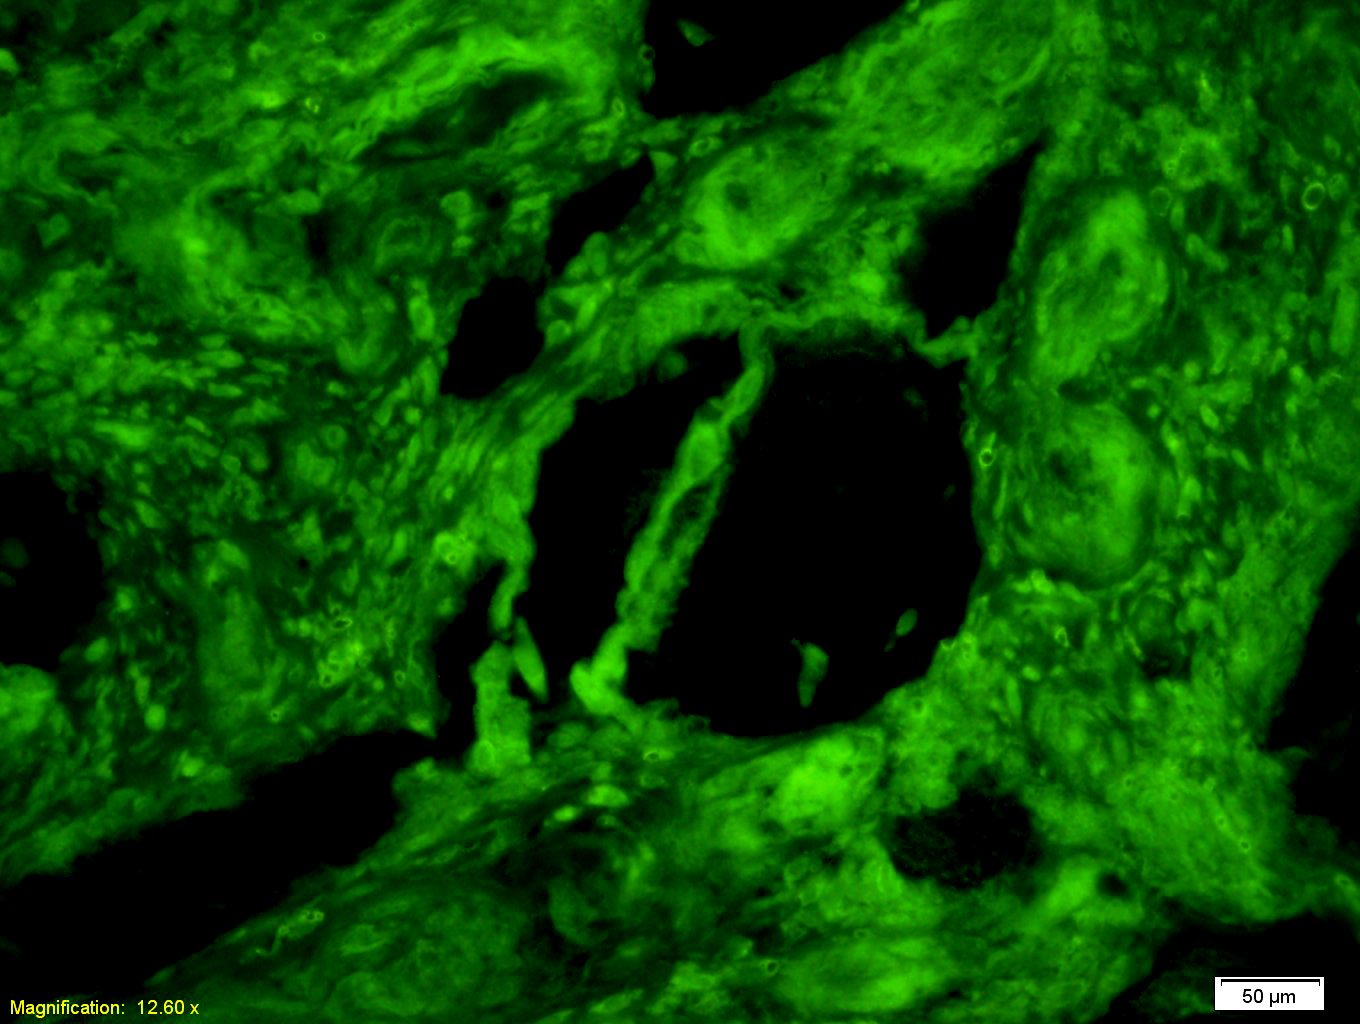

| {IHC-F} | {1:100-500} |

Antigen retrieval: citrate buffer ( 0.01M, pH 6.0 ), Boiling bathing for 15min; Blocking buffer (normal goat serum,C-0005) at 37℃ for 20 min;

Incubation: Anti-PKM2 Polyclonal Antibody, Unconjugated(bs-0101R) 1:200, overnight at 4°C; The secondary antibody was Goat Anti-Rabbit IgG, FITC conjugated(bs-0295G-FITC)used at 1:200 dilution for 40 minutes at 37°C.